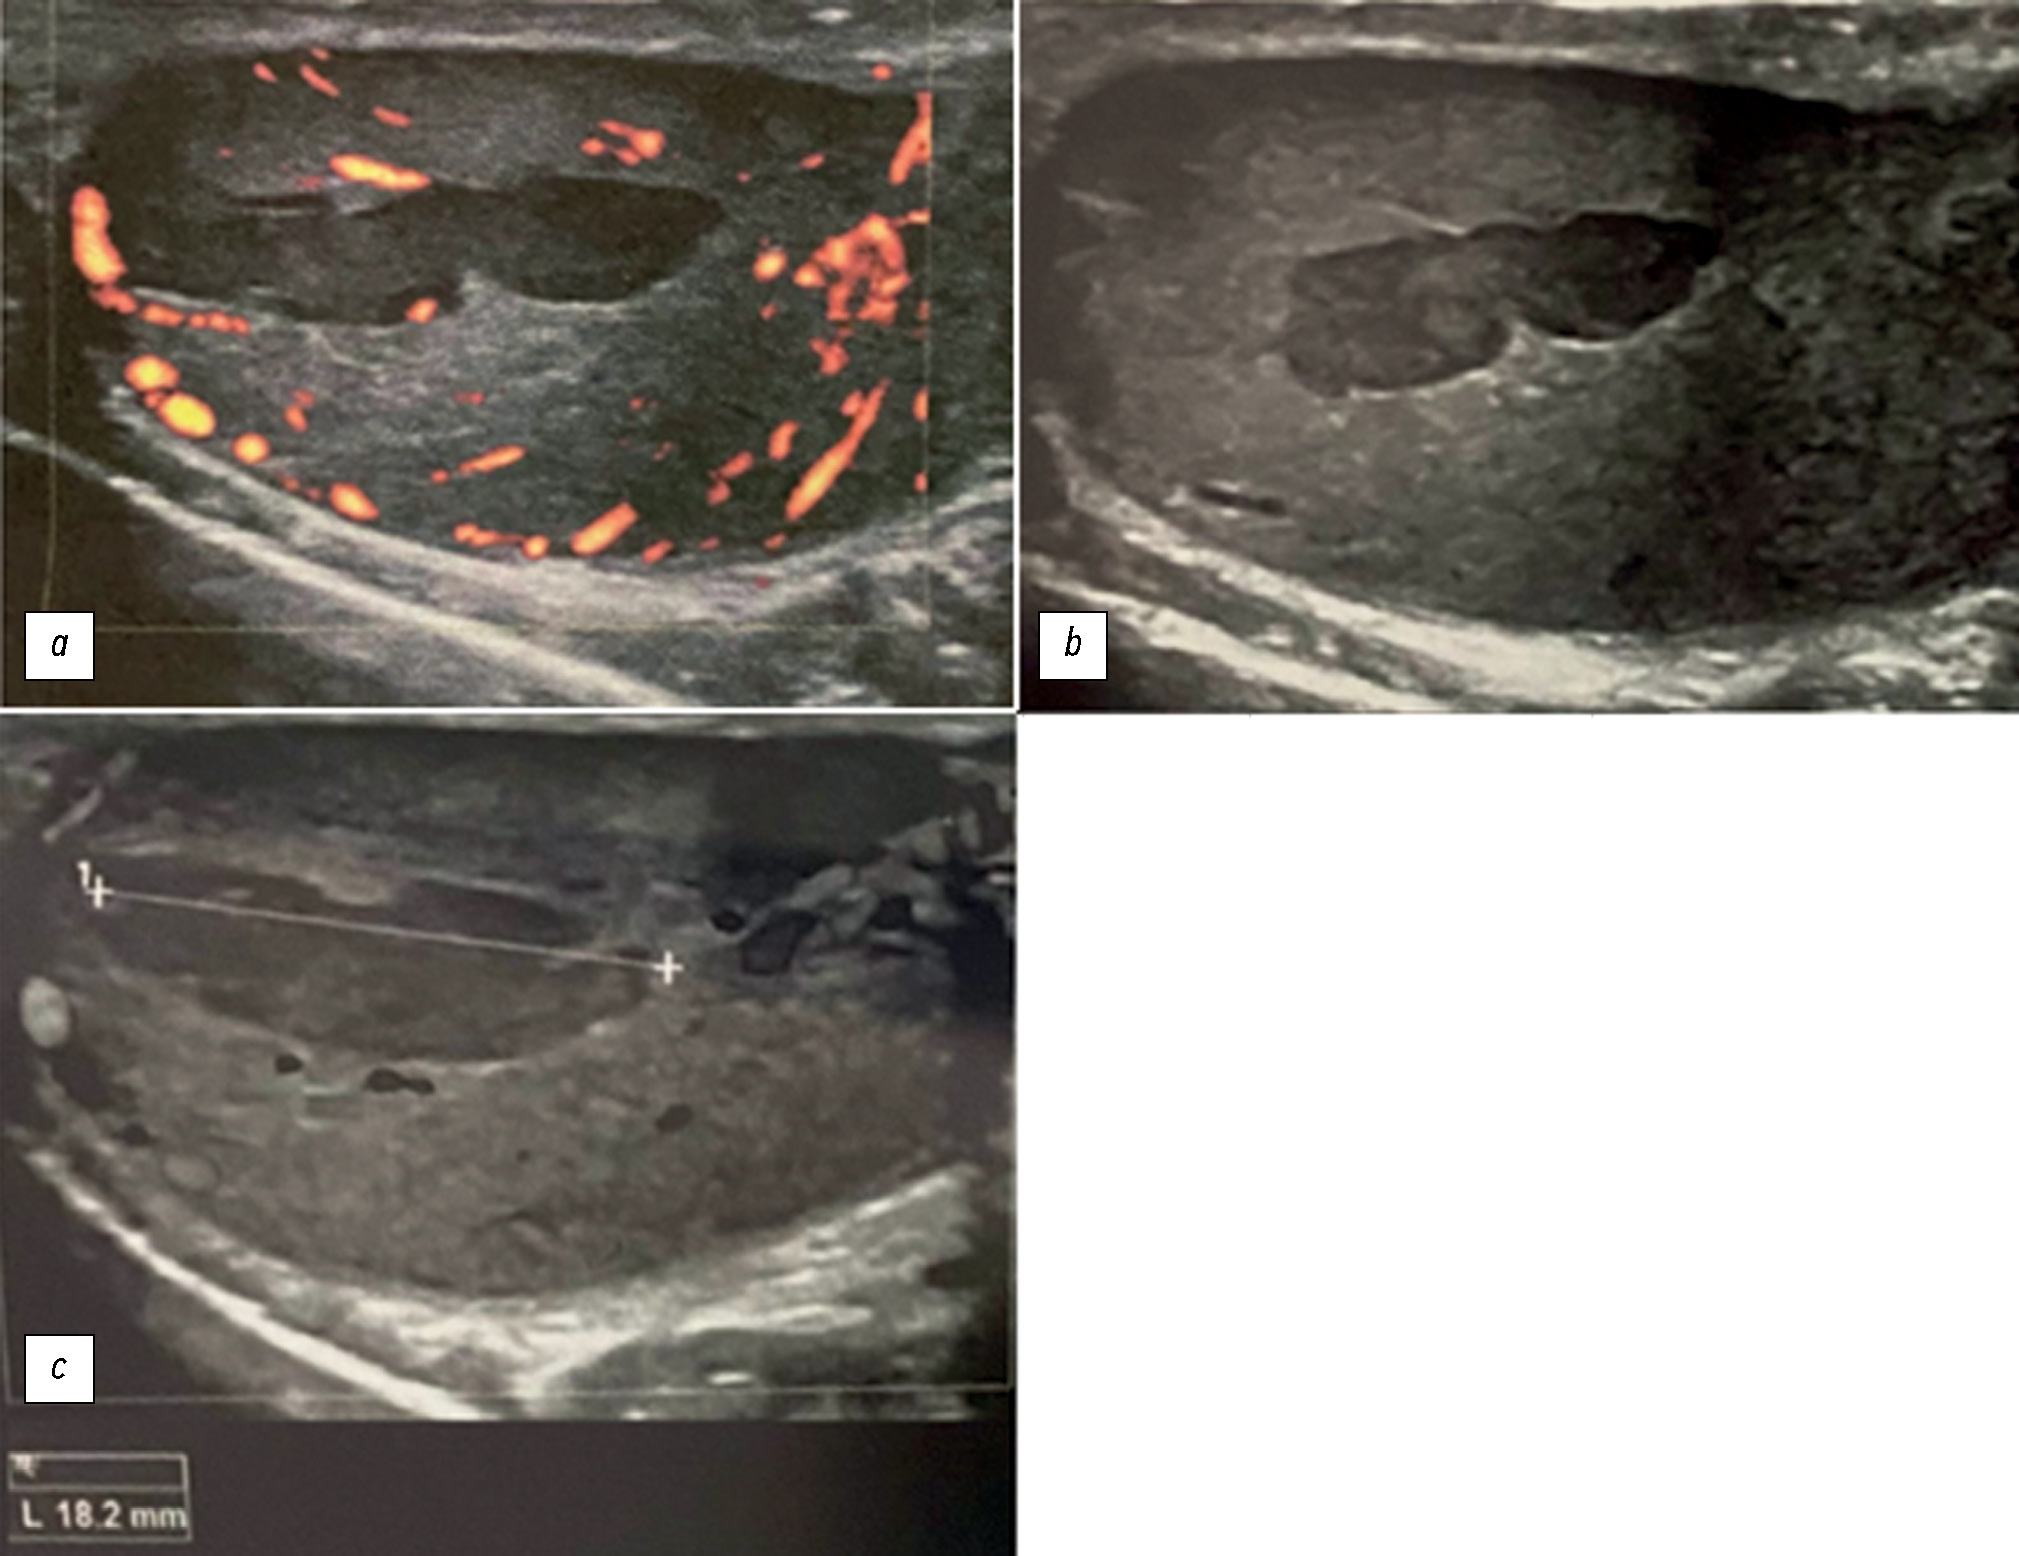

В редких случаях острый эпидидимит сопровождается развитием ишемии и инфаркта яичек. Отличить эпидидимит от перекрута яичка по клиническим признакам и результатам визуализации достаточно непросто. В данной статье мы постарались расширить библиотеку цифровых изображений методов лучевой диагностики, используемых для быстрой и точной дифференциальной диагностики. Представленный случай подчёркивает важность комплексного лучевого обследования и необходимость междисциплинарного подхода для постановки точного диагноза. Мужчина, 24 года, обратился в больницу по поводу сильной боли в левом яичке, возникшей 2 недели назад. Со слов пациента, в течение некоторого времени у него наблюдались болезненные эякуляции, боль во время полового акта (диспареуния), покраснение/припухлость мошонки, воспаление половых органов, озноб, увеличение паховых лимфатических узлов, дизурия и боль в мошонке. По направлению уролога были проведены ультразвуковое исследование и магнитно-резонансная томография. Визуализационные исследования показали наличие ишемии левого яичка. С учётом данных анамнеза возникло подозрение на хронический орхоэпидидимит. Поскольку зона ишемии была ограниченной, пациенту не потребовалось проведения левосторонней орхидэктомии. Была назначена медикаментозная терапия. Кроме того, у пациента было выявлено левостороннее варикоцеле. Было проведено тщательное изучение изображений, полученных в различных последовательностях магнитно-резонансной томографии. В настоящей работе описан редкий случай орхоэпидидимита, который представляет собой потенциально опасное осложнение эпидидимита. Во избежание серьёзных последствий вероятность данного осложнения следует учитывать при возникновении внезапной сильной боли в мошонке. В описании данного случая представлена информация, которая позволит оптимизировать подходы к ведению пациента и избежать ненужных вмешательств.